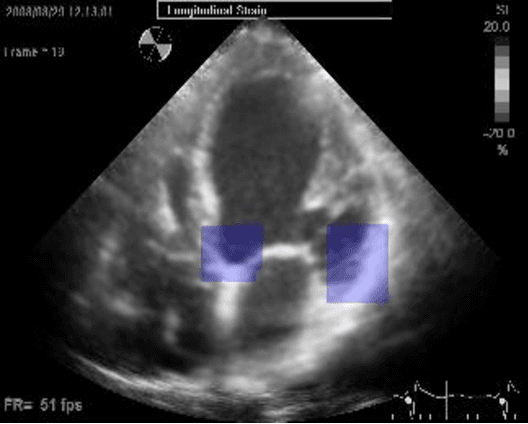

Abstract:Left ventricular segmentation is essential for measuring left ventricular function indices. Segmentation of one or several images requires an initial guess of the contour. It is hypothesized here that creating an initial guess by first detecting anatomical markers, would lead to correct detection of the endocardium. The first step of the algorithm presented here includes automatic detection of the mitral valve. Next, the apex is detected in the same frame. The valve is then tracked throughout the cardiac cycle. Contours passing from the apex to each valve corner are then found using a dynamic programming algorithm. The resulting contour is used as an input to an active contour algorithm. The algorithm was tested on 21 long axis ultrasound clips and showed good agreement with manually traced contours. Thus, this study demonstrates that detection of anatomic markers leads to a reliable initial guess of the left ventricle border.